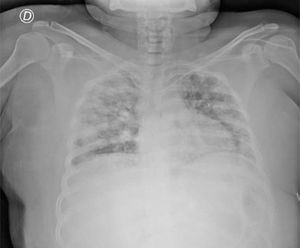

Presentamos el caso de una paciente de sexo femenino de 23 años con antecedente de diabetes mellitus tipo 2 que ingresa a urgencias por presentar dolor abdominal difuso, náuseas, vómito y fiebre de 3 días de evolución. El dolor se intensifica, irradiándose a epigastrio e hipocondrio derecho. Presentaba signos vitales de 131 latidos por minuto, 24 respiraciones por minuto, tensión arterial de 110/60mmHg y 38.6 ̊C de temperatura. A la exploración física presentaba ruidos crepitantes bibasales, abdomen con dolor difuso a la palpación abdominal con datos de irritación peritoneal. Los análisis de laboratorio reportaron una leucocitosis de 19,280cel/mm3 con neutrófilos de 79.8%. La glucosa al ingreso fue de 489mg/dl. El resto de los análisis de laboratorio eran normales. Se solicitó una radiografía de tórax, la cual reportó múltiples infiltrados bilaterales (fig. 1). Se realizó una tomografía computarizada simple de tórax y abdomen, en donde se reportó un grande absceso hepático roto de 6×7.1×3cm, formador de burbujas de gas en el lóbulo hepático derecho, sin presentar rotura diafragmática o datos de continuidad a tórax, además de neumoperitoneo con líquido libre en ambas correderas parietocólicas (fig. 2a). En el tórax se reportaron múltiples nódulos pulmonares cavitados compatibles con embolismos sépticos (fig. 2b). La paciente no había sido atendida previamente, por lo que se comenzó con administración de antibióticos de amplio espectro; sin embargo, el cuadro clínico empeoró de forma rápida, instaurándose un choque séptico que requirió vasopresores. Se llevó a la paciente a quirófano donde se realizó laparotomía de urgencia, encontrándose aproximadamente 1l de material purulento en la cavidad abdominal del cual se tomaron cultivos. Se tomó biopsia hepática para descartar malignidad. Se drenó el absceso identificado en el segmento iv y la paciente pasó en estado crítico a terapia intensiva. La paciente falleció 10h posteriores a su procedimiento quirúrgico. El resultado del cultivo reportó K. pneumoniae y la biopsia hepática reportó material fibrinopurulento.